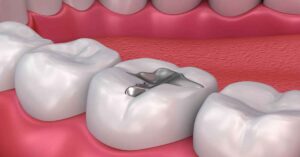

Diş hekimliğinde uzun yıllardır kullanılan ve çürük dişlerin tedavisinde tercih edilen bir dolgu malzemesidir. Amalgam dolgu nedir? Halk arasında “gümüş dolgu” olarak da bilinen amalgam, gümüş, kalay, bakır ve az miktarda cıva gibi metallerin karışımından elde edilir. Bu alaşım, dayanıklılığı ve kolay uygulanabilirliği sayesinde günümüze kadar en sık kullanılan dolgu türlerinden biri olmuştur.

Diş hekimliğinde en uzun süredir kullanılan dolgu materyallerinden biridir. “Gümüş dolgu” olarak da bilinen bu yöntem, dayanıklılığı ve uzun ömürlü yapısı nedeniyle özellikle arka dişlerde tercih edilmektedir. Günümüzde estetik kaygılar sebebiyle alternatif dolgu türleri öne çıkmıştır. Ancak amalgam malzemeli dolgunun sunduğu avantajlar önemini korumaktadır.

Amalgam dolgu, diş hekimliğinde uzun yıllardır kullanılan ve “gümüş dolgu” olarak da bilinen bir dolgu türüdür. İçeriğinde gümüş, bakır, kalay ve belirli oranda cıva bulunur. Bu metallerin birleşimi, amalgama dayanıklı ve uzun ömürlü bir yapı kazandırır. Özellikle arka dişlerde, yani çiğneme kuvvetinin en yoğun olduğu bölgelerde tercih edilen bir yöntemdir.

Rengi gri-siyah tonlarındadır. Bu nedenle estetik açıdan özellikle ön dişlerde tercih edilmez. Ancak sağlamlığı sayesinde arka dişlerde uzun vadeli koruma sağlar.